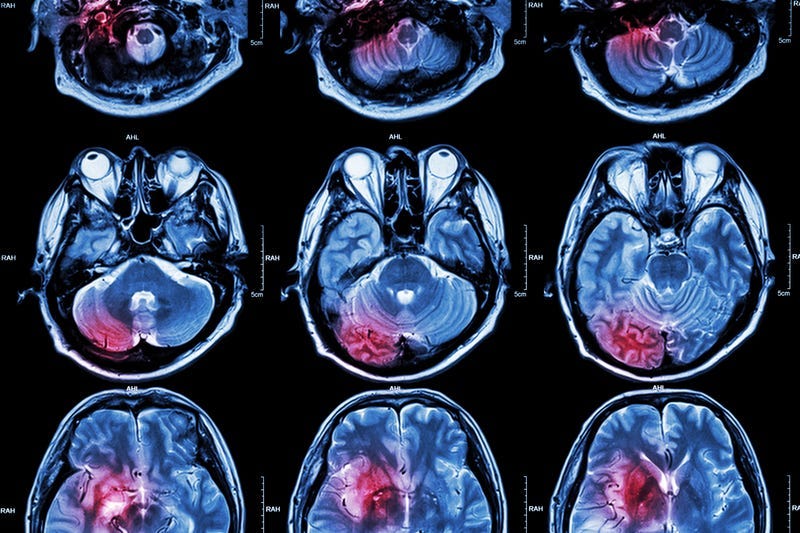

PHILADELPHIA (KYW Newsradio) — When a person suffers a stroke, it can have a devastating impact.

According to a new study, the impact can be quite different for a man or a woman who suffered from a stroke. Researchers found that women are twice as likely as men to suffer from severe depression after a stroke.